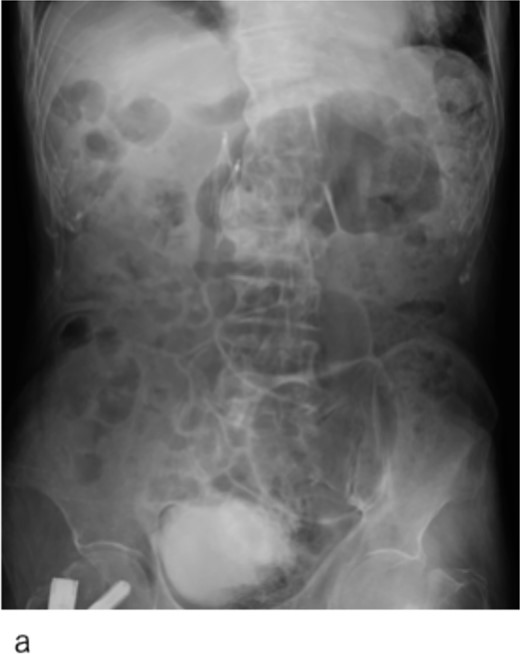

A 93-year-old man was admitted to our emergency clinic with a left femoral fracture. He presented with severe hypoxemia and shock. Treatment included high-density oxygen administration using noninvasive positive pressure ventilation (NPPV), fluid resuscitation, and epinephrine administration. Duplex ultrasonography revealed deep venous thrombosis (Fig. 1a). Computed tomography of the enhanced pulmonary artery and lower extremity veins revealed pulmonary thromboembolism and deep venous thrombosis in the left superficial femoral and popliteal veins (Fig. 1b and c). Echocardiography revealed right ventricular dilation and pulmonary hypertension at 43 mmHg. D-dimer and NT-proBNP levels significantly increased to 48 and 1941 pg/ml, respectively. Immediate heparin administration was contraindicated because the patient was at risk of hemorrhage from the femoral fracture. IVCF implantation was recommended.

(a) Duplex ultrasonography image of the left superficial vein on admission. A thrombus is observed in the vein. (b) Enhanced computed tomography on admission. Left popliteal venous aneurysm (arrow). A thrombus is observed in the aneurysm (*). (c) Enhanced computed tomography on admission. A pulmonary embolism is observed (arrow)